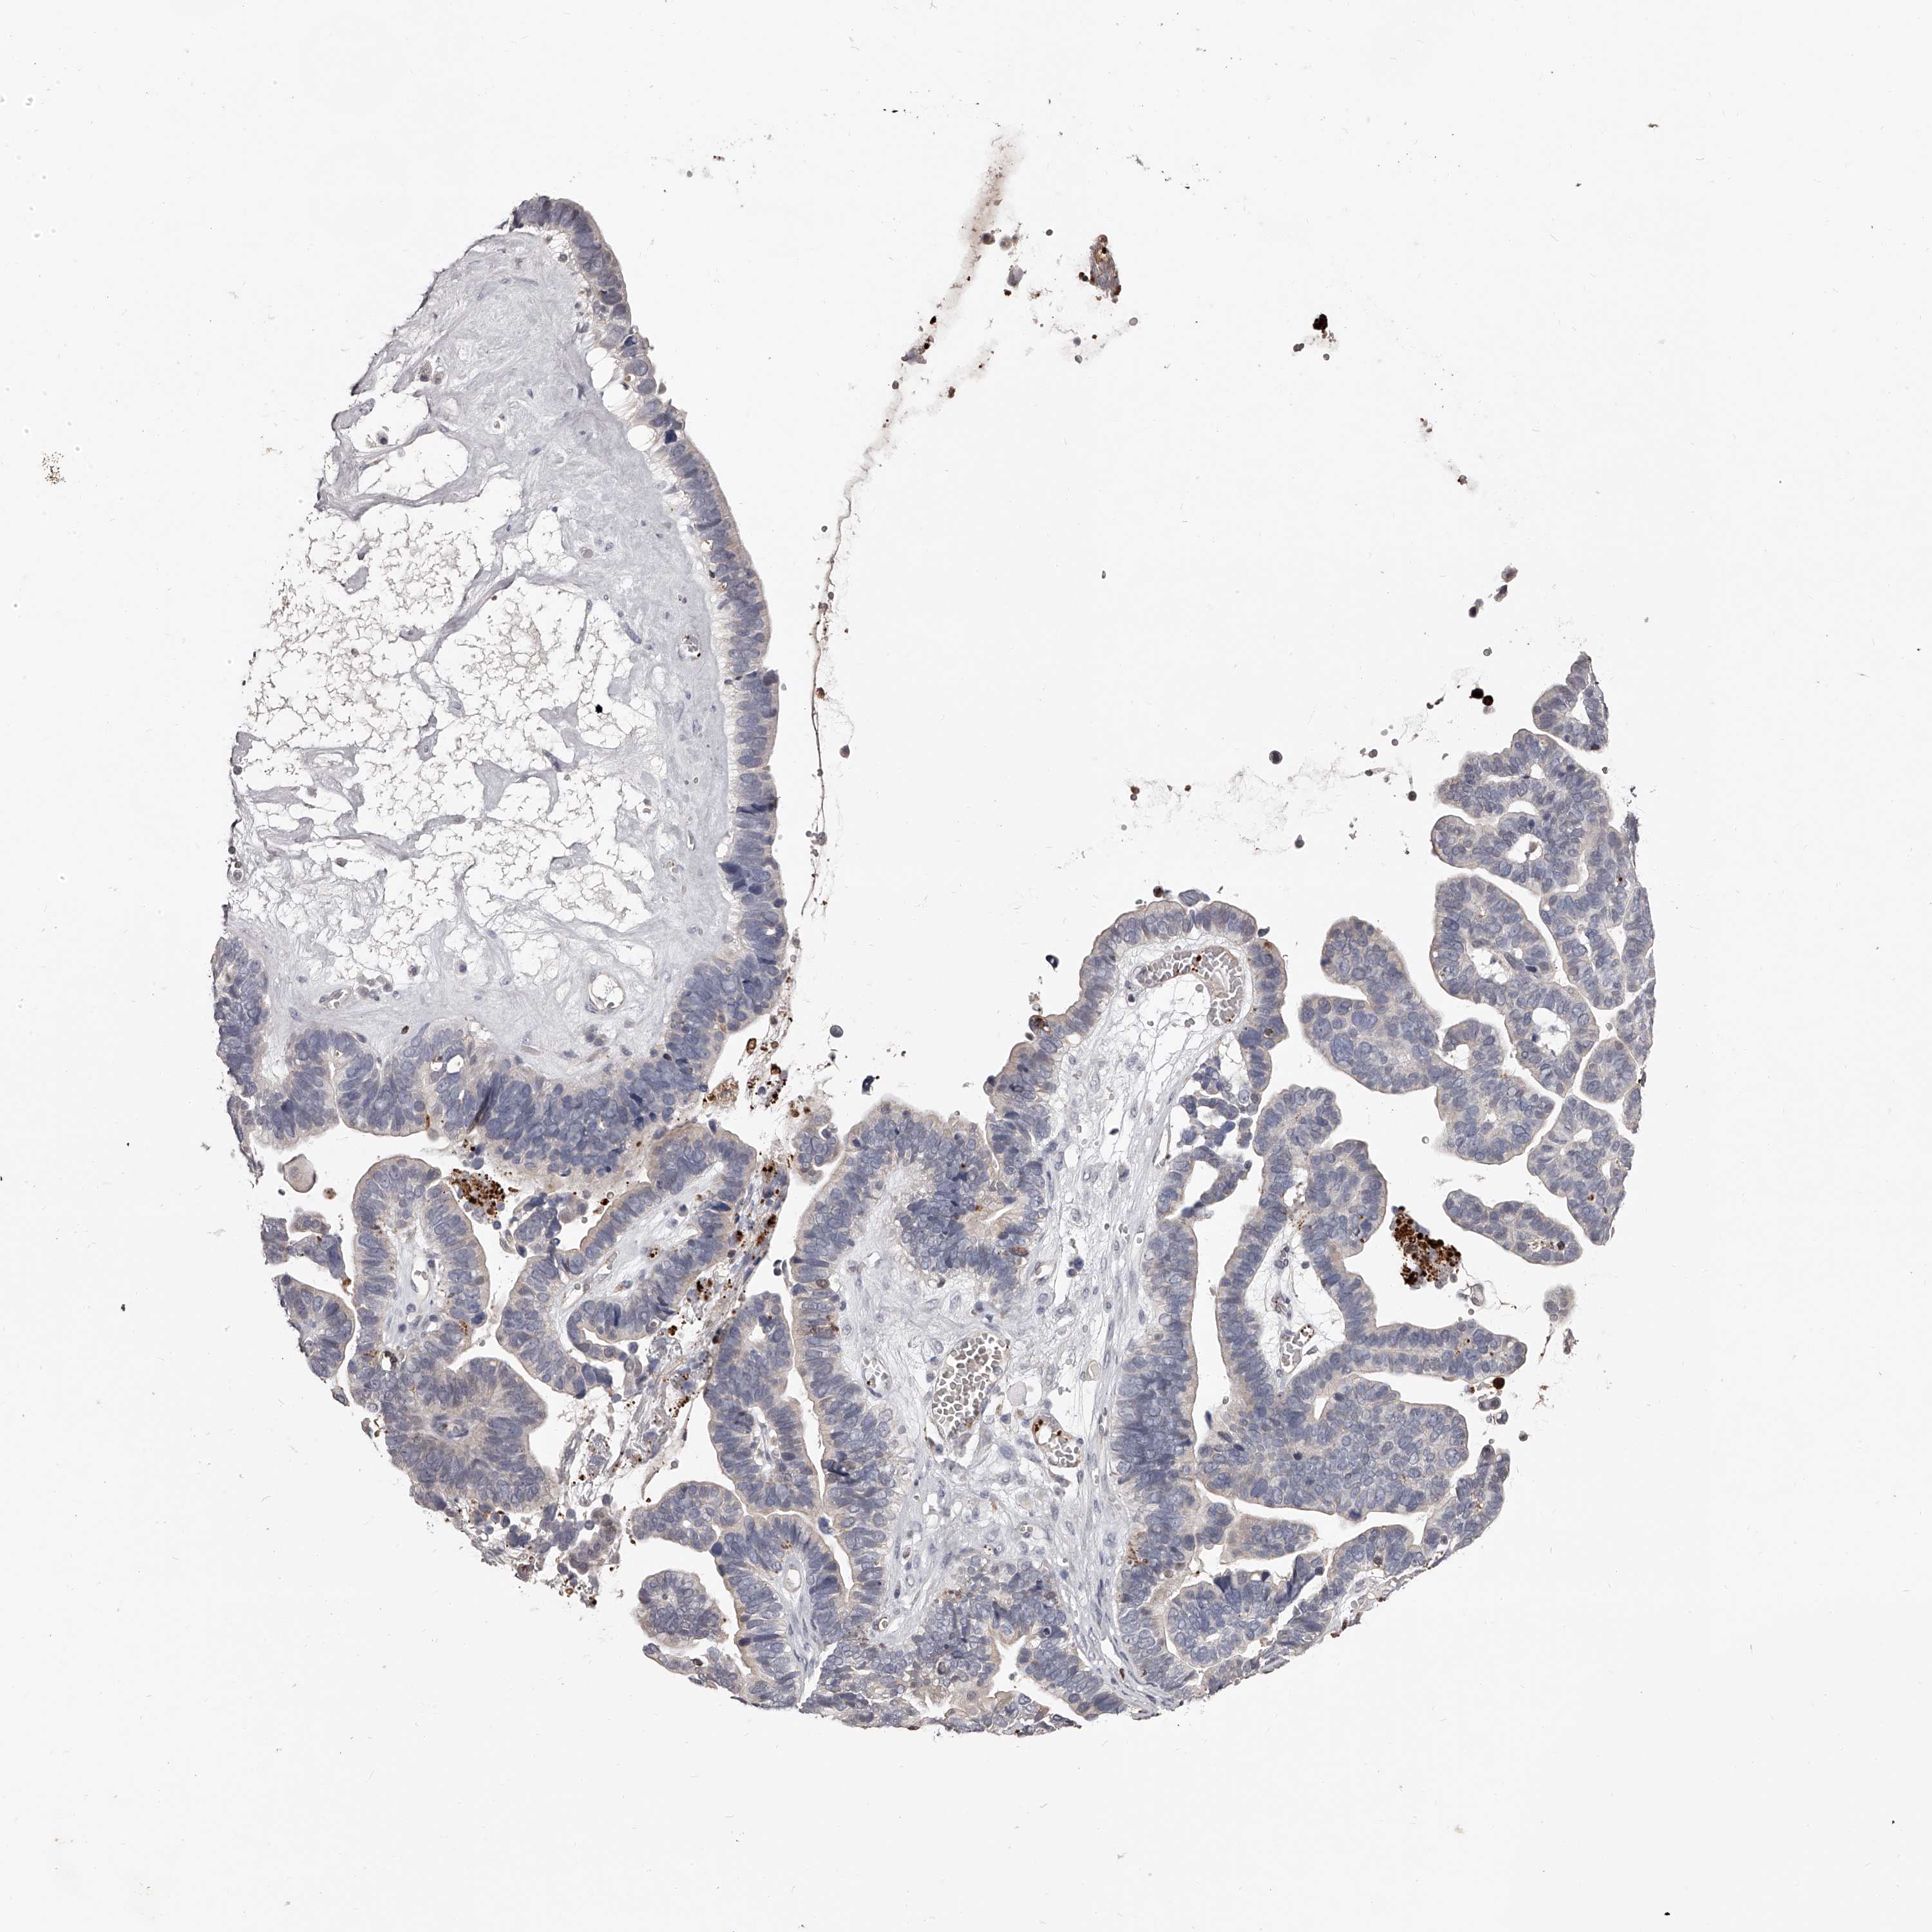

OVARIAN CANCER - Protein expressioni

A mouse-over function shows sample information and annotation data. Click on an image to view it in a full screen mode. Samples can be filtered based on level of antibody staining by selecting one or several of the following categories: high, medium, low and not detected. The assay and annotation is described here.

Note that samples used for immunohistochemistry by the Human Protein Atlas do not correspond to samples in the TCGA dataset.

Antibody stainingi

Antibody staining in the annotated cell types in the current human tissue is reported as not detected, low, medium, or high, based on conventional immunohistochemistry profiling in selected tissues. This score is based on the combination of the staining intensity and fraction of stained cells.

Each image is clickable and will lead to virtual microscopy that enables deeper exploration of all samples and also displays staining intensity scores, fraction scores and subcellular localization as well as patient and tissue information for each sample.

Antibody HPA019879

Antibody HPA020134

Antibody HPA029468

Cystadenocarcinoma, serous, NOS

Carcinoma, endometroid

Cystadenocarcinoma, mucinous, NOS

Carcinoma, NOS